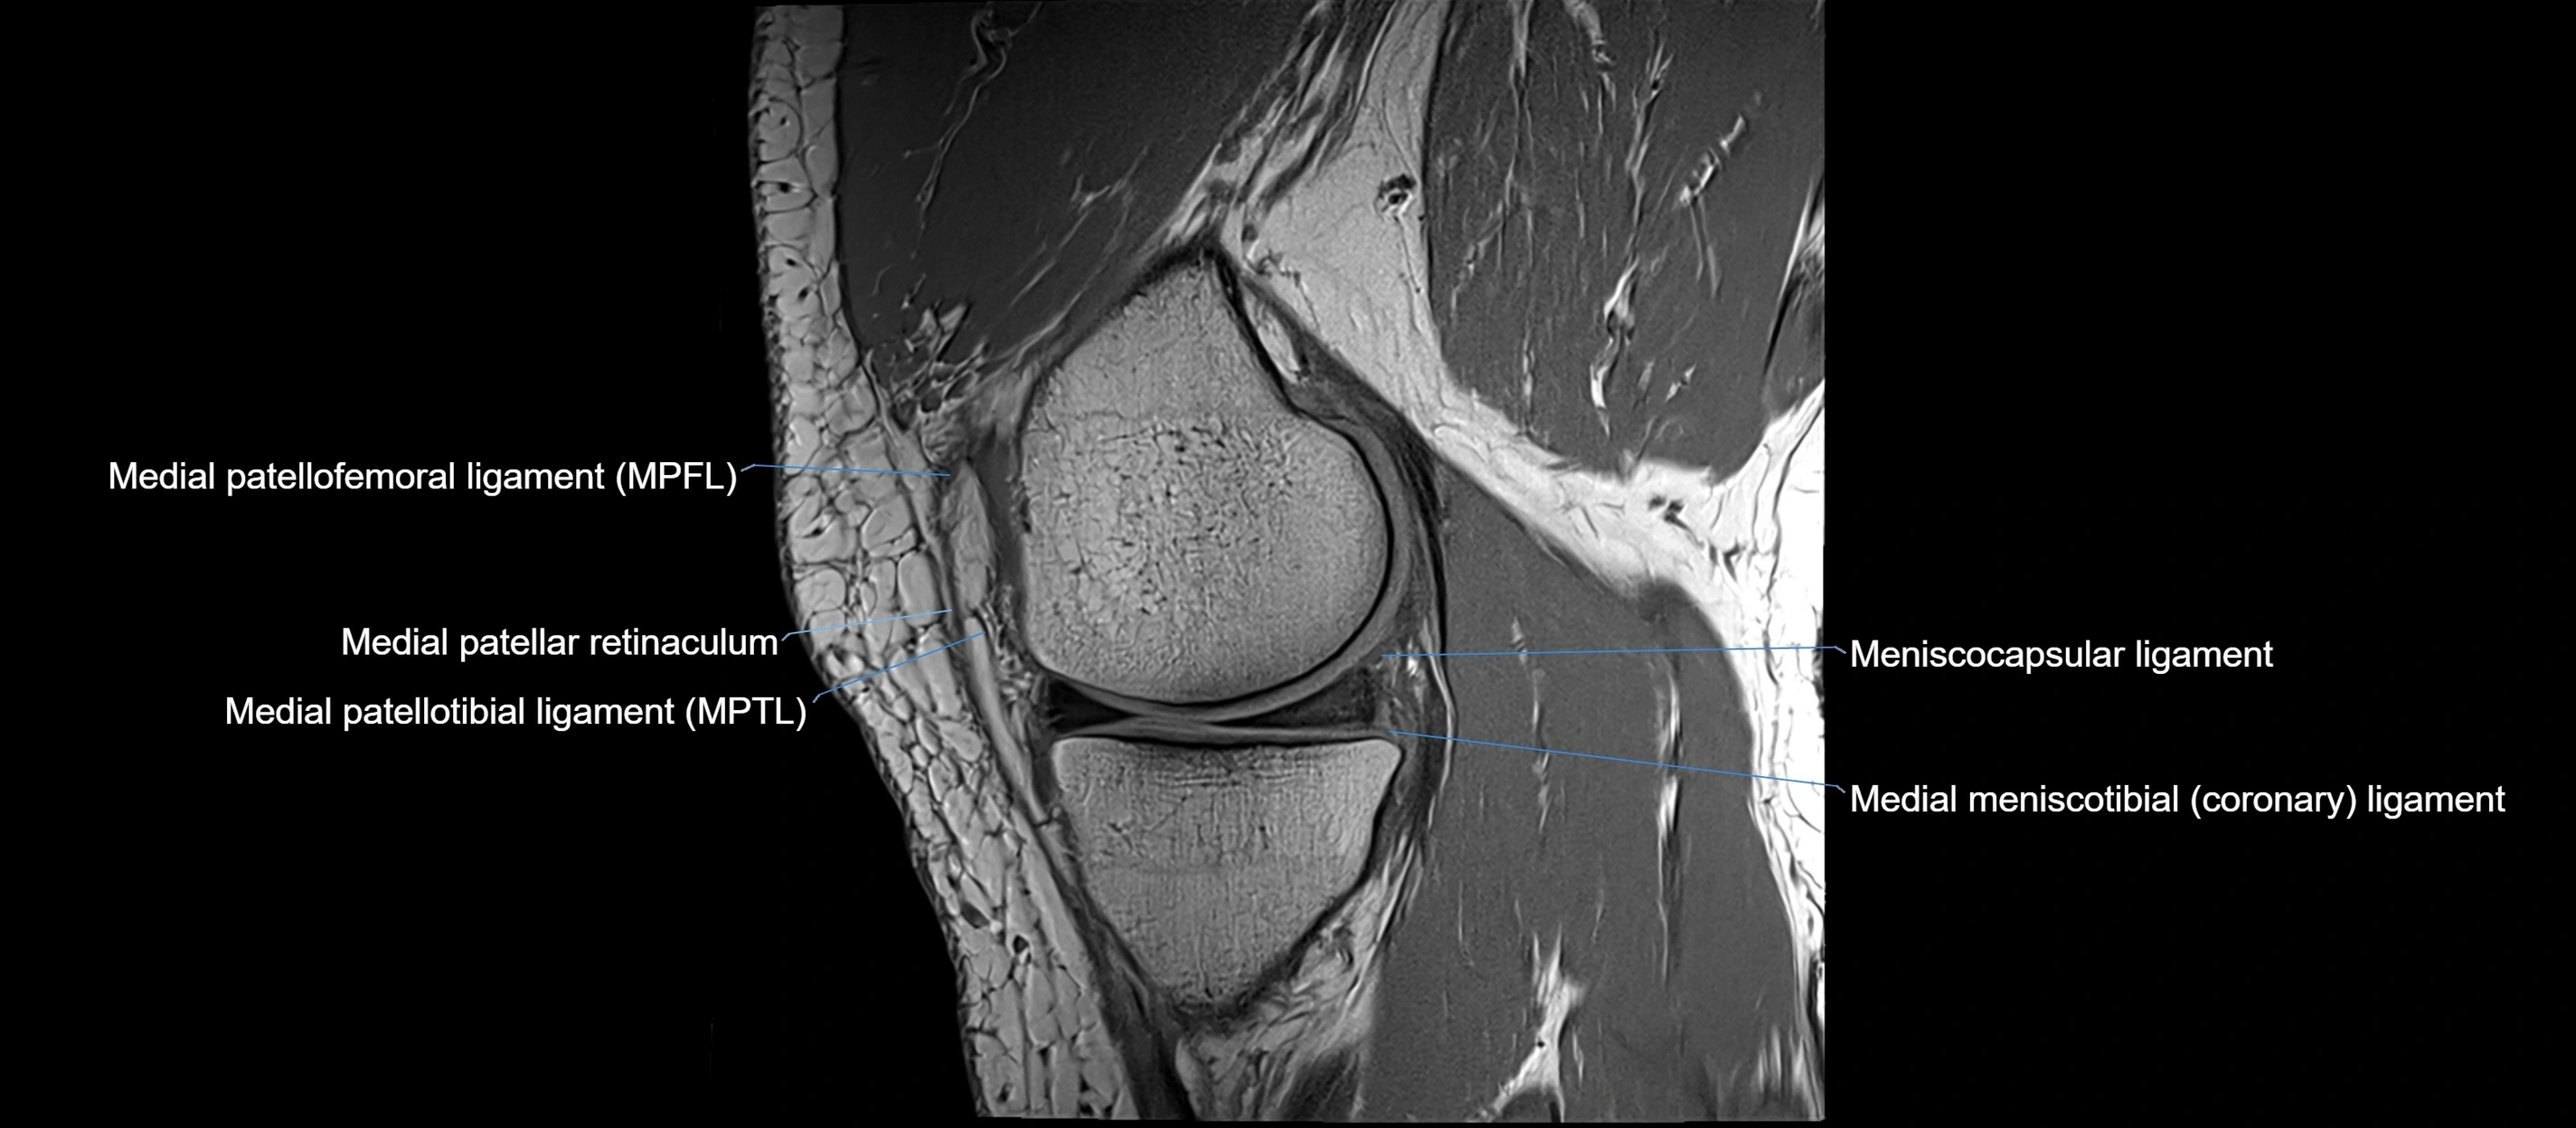

MRI images

image